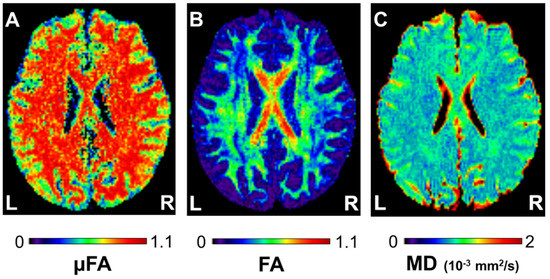

where ε is the signal variation between the parallel and orthogonal diffusion gradient pairs; b is the b-value; D is the mean diffusivity of the diffusion tensor; and λ1, λ2, and λ3 are the eigenvalues of the diffusion tensor [15,22]. Calculations were done using a custom-built software that runs on MATLAB R2009b (The MathWorks, Natick, MA, USA). Example μFA, FA, and MD maps of a subject are given in Figure 2.

Figure 2. Example (A) microscopic fractional anisotropy (μFA), (B) fractional anisotropy (FA), and (C) mean diffusivity (MD) maps of a 23−year−old man. The values are given in the corresponding look−up tables. L and R indicate left and right, respectively.